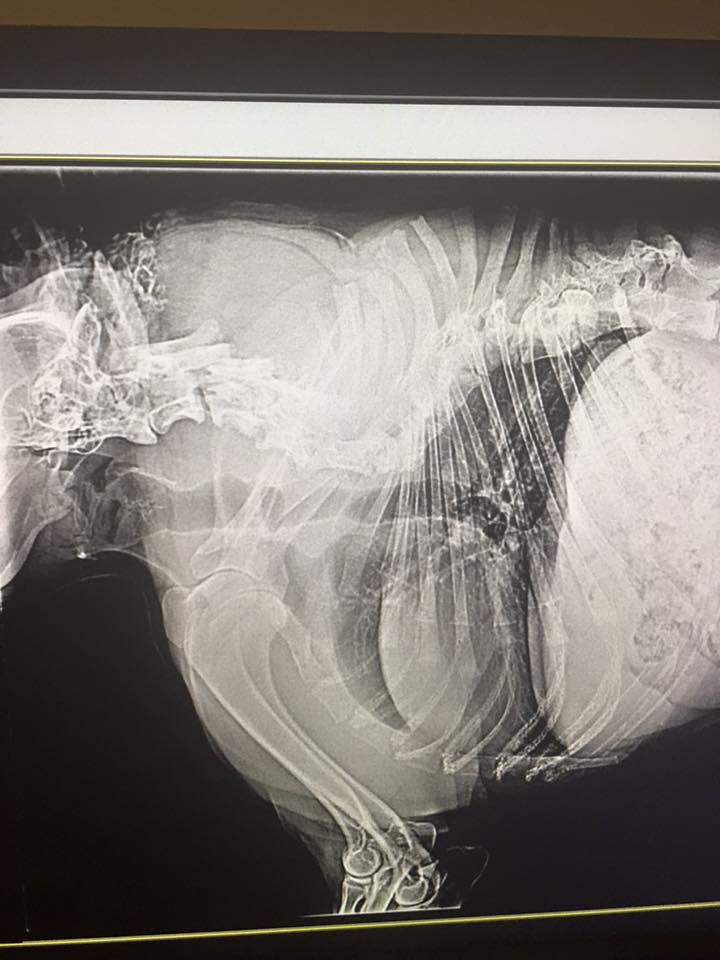

Doktor Susan Miller, która przeprowadziła badania Quasi ,w tym prześwietlenie ciała, stwierdziła, że pies ma normalnej wielkości głowę i kończyny, ale ma też poskręcany kręgosłup, brakuje mu kilkunastu kręgów, ma skurczony żołądek, jedno jądro i ogon zwinięty jak korkociąg. Jak powiedziała: „Jego narządy wewnętrzne są ściśnięte jak akordeon ”.